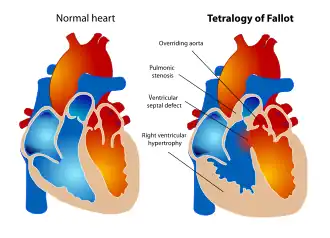

Изображение здорового сердца и сердца с тетрадой Фалло | |

Тетра́да Фалло́ — так называемый синий порок сердца, сочетающий, по определению французского врача Этьена-Луи Артура Фалло, четыре аномалии:

- стеноз выходного отдела правого желудочка (клапанный, подклапанный, стеноз лёгочного ствола и (или) ветвей лёгочной артерии либо комбинированный);

- высокий (субаортальный) дефект межжелудочковой перегородки;

- декстрапозиция аорты;

- гипертрофия правого желудочка (как следствие затруднённого оттока крови из желудочка).

Четыре анатомических компонента:

- Вентрикулосептальный дефект — дефект межжелудочковой перегородки (ДМЖП) — соединяет между собой правые и левые отделы сердца. ДМЖП при тетраде Фалло всегда большой и нерестриктивный. Как правило, это перимембранозный ДМЖП (англ. perimembranous VSD), мышечный ДМЖП (англ. muscular VSD), или юкстаартериальный (околоартериальный; лат. juxta — около, подле, рядом) ДМЖП (англ. juxtaarterial VSD).

- Обструкция исходящего отдела правого желудочка — происходит за счёт одной из перечисленных или комбинации анатомических компонентов. К ним относятся инфундибулярный (подклапанный) стеноз исходящего отдела правого желудочка, клапанный стеноз лёгочной артерии, обструкция за счёт гипертрофированного миокарда правого желудочка, гипоплазия ствола и/или ветвей лёгочной артерии [6].

- Декстропозиция аорты — аорта отходит частично от правого желудочка или кровоток в ней поддерживается доминантно за счёт работы левого желудочка.

- Гипертрофия правого желудочка сердца — гипертрофия мышечного компонента правого желудочка развивается с возрастом.